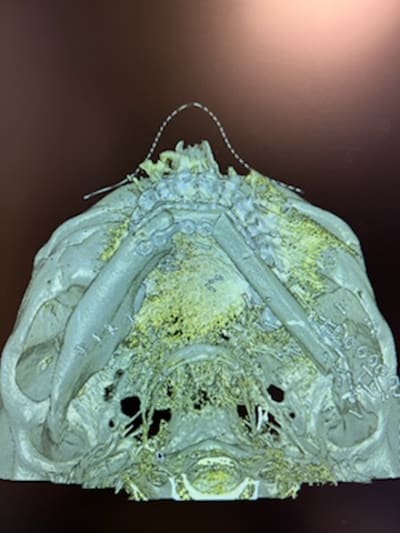

Protocole de modélisation 3D pour greffe de Fibula avec guide de coupe de péroné et d’ostéotomie mandibulaire.

Vous souhaitez découvrir les dispositifs de coupes sur mesure réalisés en acier chirurgical: [email protected]